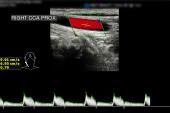

Boston Scientific has recalled its Carotid Wallstent Monorail endoprosthesis, used to treat narrowed carotid arteries, due to a manufacturing defect that increases the risk of resistance when operators remove the stent delivery system, according to a US Food and Drug Administration alert.

Affected devices have an inner lumen that is smaller than intended. As of July 29, 2025, the company reported six cases in which additional efforts were needed to recover the device, but no patients have died.